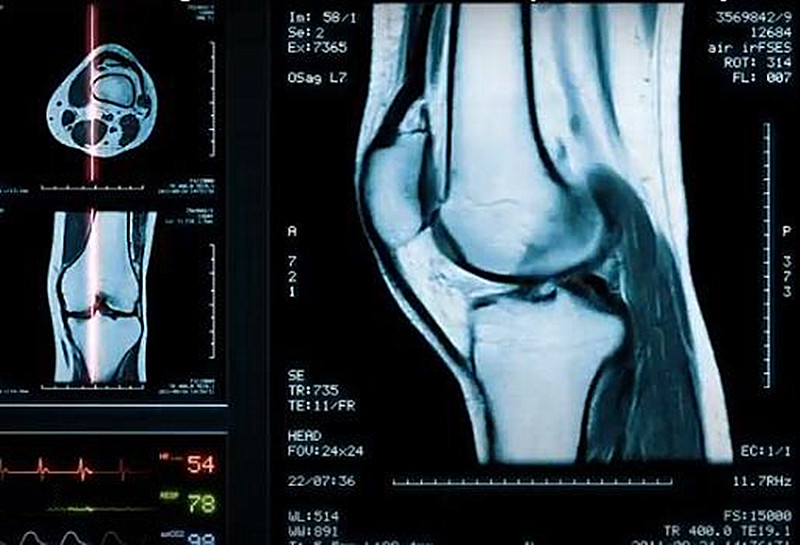

膝关节置换术后可以做核磁共振吗?

以前的一些磁共振拒绝对金属植入物的患者进行检查,因为含磁金属可能会移动,对患者造成伤害,另外某些金属也可能被电磁波加热,造成风险。磁共振图像还可能产生金属伪影,导致图像失真,影响医生的判断。

现在的磁共振技术已经不同了,同时手术前医生也会考虑到磁共振,目前的人工关节多采用无磁的钛金属,钛合金,或者含磁极低的钴铬合金,这些材料可以进行安全和准确的磁共振检查。